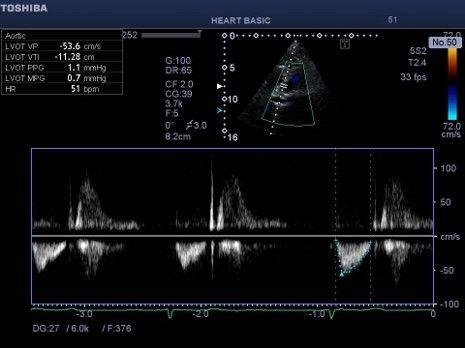

Εικόνα 6. Μικρό μήκος παλμού στην πνευμονική βαλβίδα

(ολοκλήρωμα ταχύτητας VTI 9 cm ενδεικτικό μικρού όγκου

παλμού και χαμηλής παροχής. Η μορφολογία του σήματος με το

βραχύ χρόνο επιτάχυνσης και την εγκοπή κατά της επιβράδυνση της

ροής η οποία ενδεχομένως σχετίζεται με πνευμονική υπέρταση. Σε

τέτοιες περιπτώσεις εφόσον απαιτείται κλινικά μέτρηση της πίεσης

της πνευμονικής αρτηρίας αυτή γίνεται αξιόπιστα μόνο με δεξιό

καρδιακό καθετηριασμό. Κατά τη διαστολή υπάρχει προς τα εμπρός

ροή στην πνευμονική αρτηρία (αντίθετα με το αναμενόμενο)

ενδεικτική διαστολικής δυσλειτουργίας της δεξιάς κοιλίας με

περιοριστική φυσιολογία.

Εικόνα 7. Μικρό μήκος παλμού

στην αορτική βαλβίδα (ολοκλήρωμα

ταχύτητας VTI 11.3 cm ενδεικτική μικρού όγκου παλμού. Η

ασθενής έχει προχωρημένη καρδιακή ανεπάρκεια με διατηρημένο

κλάσμα εξώθησης με πνευμονική και συστηματική συμφόρηση και

χαμηλή καρδιακή παροχή στην ηρεμία.